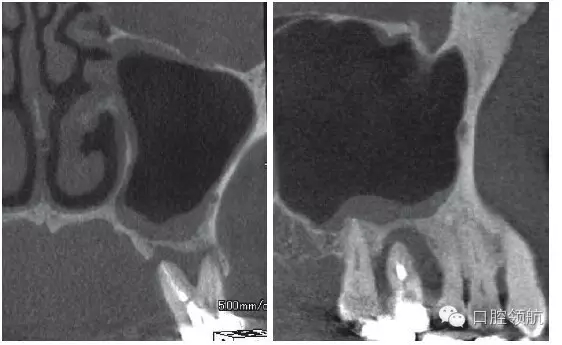

患者,78歲,男性 ,因6 牙齦腫脹來院,檢查見牙根周圍因牙槽骨缺損表現(xiàn)為透過影像(圖1)。在制訂治療計劃時,對于因重度牙周炎、慢性根尖周炎、牙根折斷等原因導致的牙齒缺失需要行上頜竇底提升術的病例,不能單純考慮缺牙區(qū),要同時考慮鄰牙狀態(tài),并用CBCT確認上頜竇底黏膜是否有增厚,這是非常重要的。該病例,根據(jù)CBCT能夠觀察到上頜竇底黏膜增厚,拔牙即刻植入感染幾率較高。計劃拔牙后4~8周,拔牙窩牙齦上皮愈合但拔牙窩未消失時(拔牙后早期植入)植入種植體(圖2)。

圖1 CBCT影像確認是由6 引起的上頜竇底黏膜增厚。